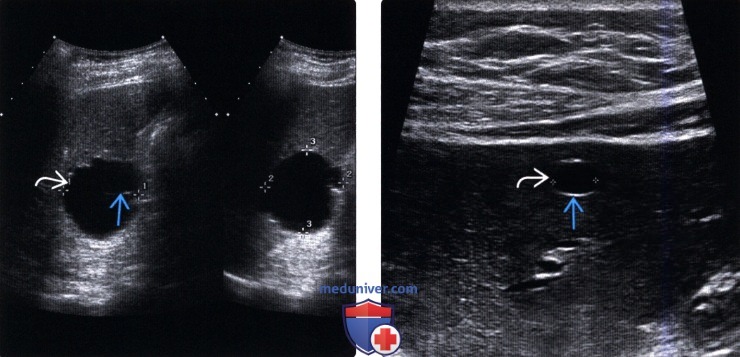

Среди специальных методов диагностики безусловное преимущество имеет ультразвуковое исследование. Его диагностическая точность колеблется в пределах 90—100%. Метод позволяет выявлять кисты диаметром более 5 мм. Он прост, доступен и неинвазивен. Непаразитарные кисты печени определяются как округлые образования с четкой капсулой, хорошо пропускающей ультразвуковые волны.

УЗИ. Киста печени

УЗИ. Описторхозные кисты печени